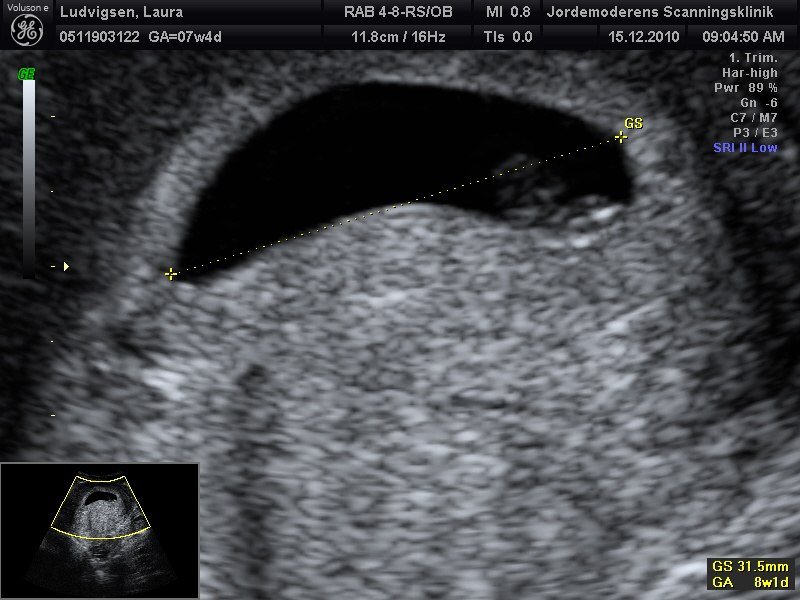

Billede 1 7+0 (Side billede)